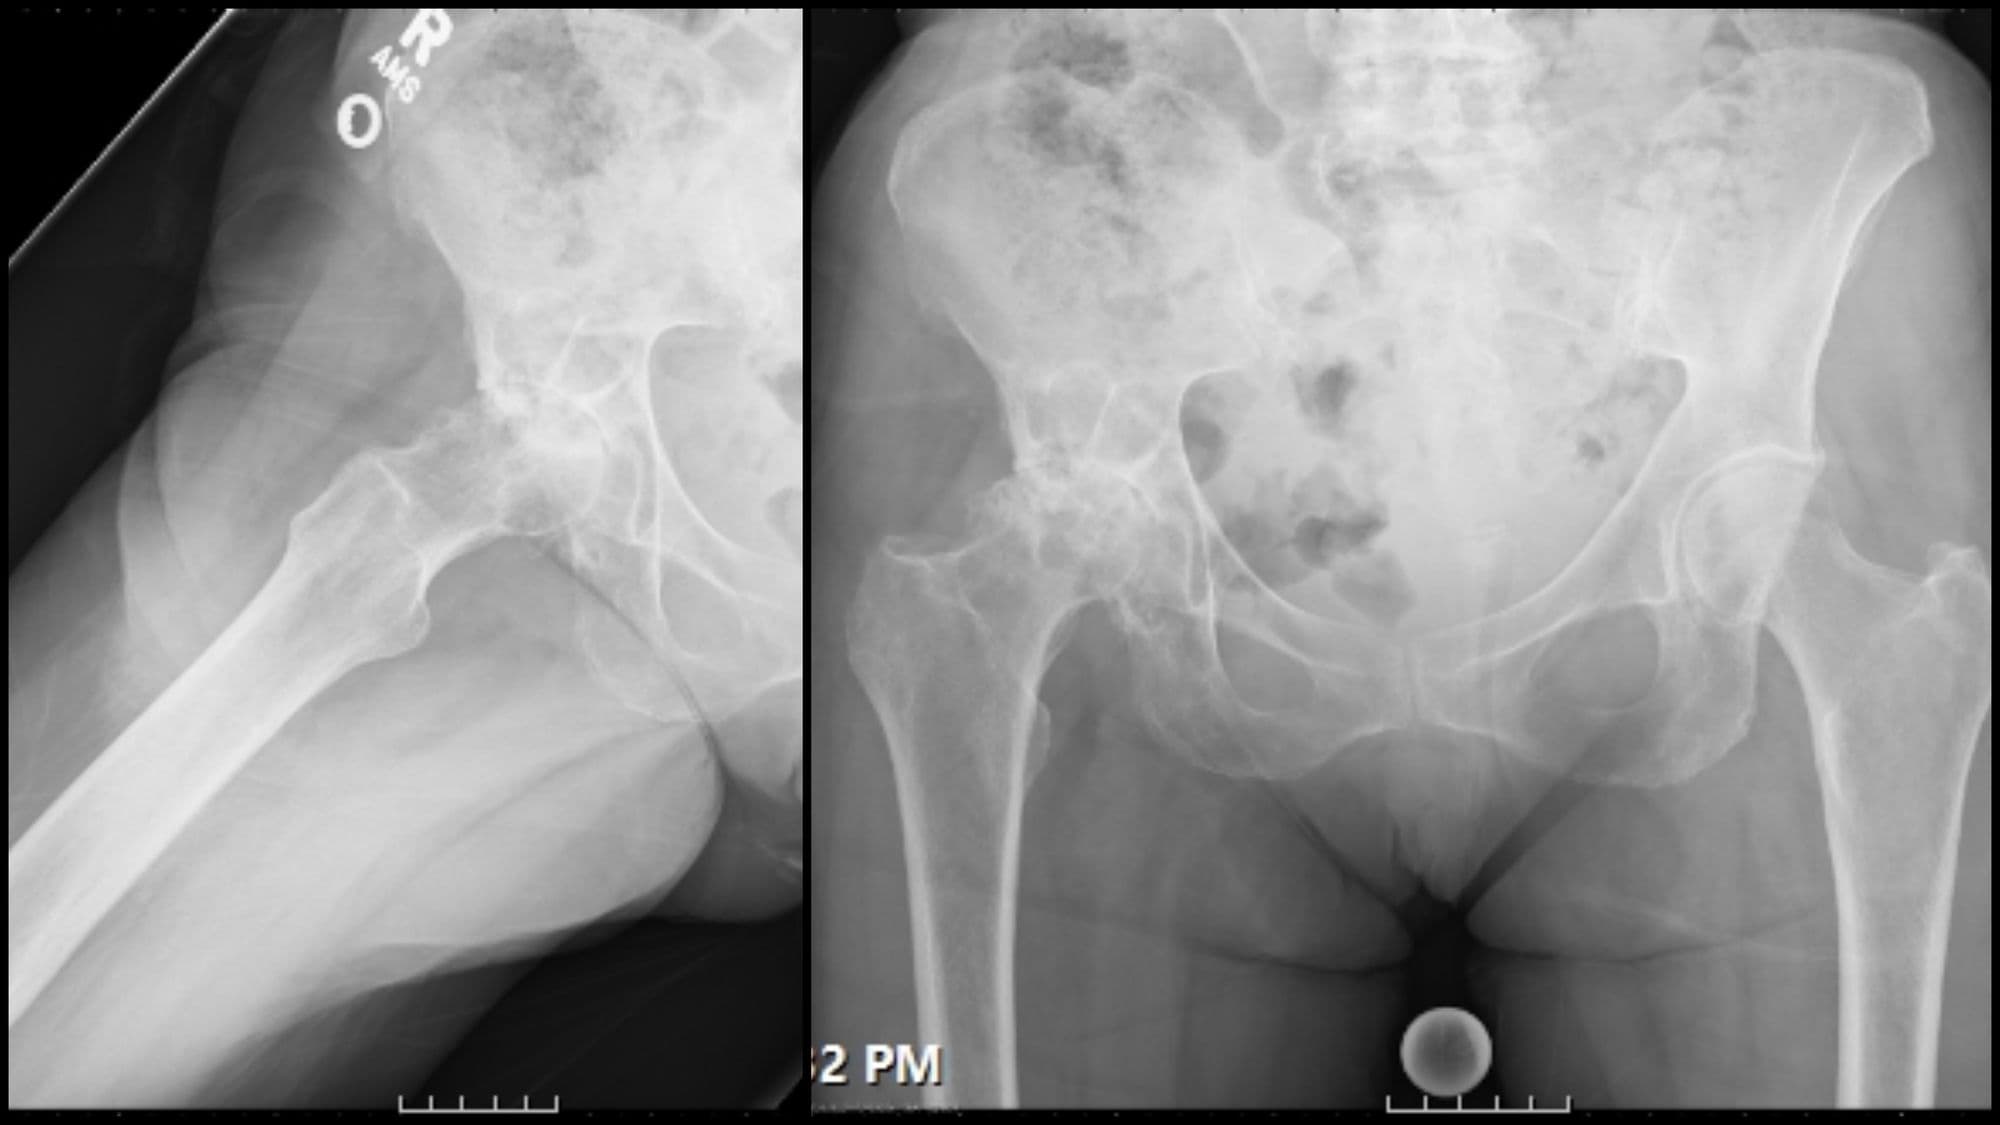

Total Hip Arthroplasty (Anterior)

John Horberg, James Lieber

Total Hip Arthroplasty (Posterior)

Adam Sassoon